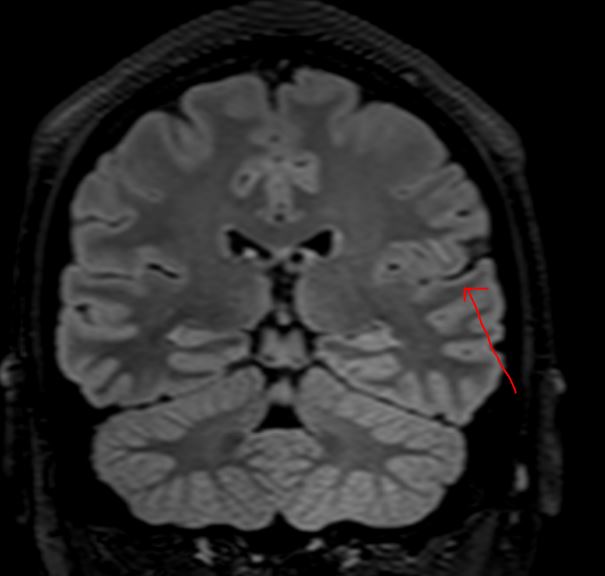

The MRI demonstrates a juxta-cortical, linear lesion in the white matter of the left post central gyrus extending medially to above the insular cortex. There is no mass effect and no enhancement. The nature of the lesion is unclear and does not relate to any of his symptomatology. His loss of consciousness almost certainly was related to a very large binge on alcohol, with very high blood alcohol levels. There is no history of any right facial or any other sensory symptomatology, nor of any episodic or persistent language dysfunction. There is no history of previous cranial trauma. His perinatal and developmental history is unremarkable.

In addition to the above lesion there are a few other punctate white matter lesions. It is presumed that these are old and have been discovered coincidentally as they do not relate to any past or recent symptomatology and are therefore "asymptomatic". I discussed the case with experienced neuroradiologist who reports that the lesions appear "innocuous".  The case also makes the point that diagnostic tests may result in a lot of harm; in this instance the patient was effectively "medically deported" within 24 hours of the scan having been done in a highly developed country. If the EEG is misinterpreted, the patient's problems will only be compounded. His EEG was normal for 72 hours; the rationale for performing it for this duration will be discussed at a later stage